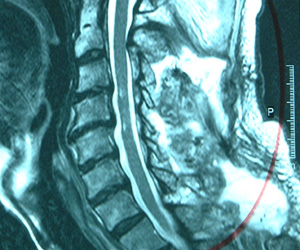

| 水平断面 (頸椎第5番/6番) |

![]() |

| 所見 | 脊柱管が狭く、脊髄は圧迫されブーメラン状に変形している。 | 脊髄は本来の姿である楕円形状に戻り、除圧されていることがわかる。 |